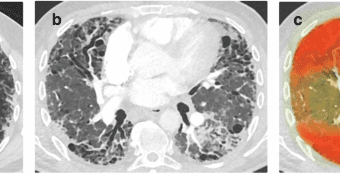

Orchestrating explainable artificial intelligence for multimodal and longitudinal data in medical imagingnpj Digital Medicine - (Tuesday July 23, 2024) - AI/ Frequent Updates/ npj Digital Medicine | |

![]() | Explainable artificial intelligence (XAI) has experienced a vast increase in recognition over the last few years. While the technical developments are manifold, less focus has been placed on the clinical applicability and usability of... Summary: #Introduction The blog post discusses the importance of explainable artificial intelligence (XAI) in medical imaging for analyzing multimodal and longitudinal data. XAI is crucial for ensuring transparency and trust in AI-driven healthcare solutions.#Challenges in Medical Imaging Medical imaging poses unique challenges for AI due to the complexity of multimodal and longitudinal data. XAI helps address these challenges by providing interpretable results and insights.#Benefits of XAI in Healthcare XAI offers several benefits in healthcare, including improved decision-making, enhanced patient care, and increased efficiency in diagnosing and treating diseases.#Applications of XAI in Medical Imaging XAI can be applied in various areas of medical imaging, such as image segmentation, disease classification, and As a healthcare IT expert, write a 50-80 extractive summarization summary for social media platforms, that is focused, accurate, and strictly reflects the content based on a blog post from the given URL. The summary should include all headings from the blog post, with inline hashtags for each heading. When including the inline hashtags, use specific hashtags related to the headings rather than generic healthcare or technology hashtags. If the headings in the blog post are too long or unclear, feel free to rephrase them into shorter, clearer versions that still convey the main idea. The target audience is other healthcare IT professionals.Following is the title and url. Orchestrating explainable artificial intelligence for multimodal and longitudinal data in medical imaging https://www.nature.com/articles/s41746-024-01190-w { "id": "chatcmpl-9ntoKUtQC0w9IGV0aNaf3JfCDN6hp", "object": "chat.completion", "created": 1721679636, "model": "gpt-3.5-turbo-0125", "choices": [ { "index": 0, "message": { "role": "assistant", "content": "Summary:n#IntroductionnThe blog post discusses the importance of explainable artificial intelligence (XAI) in medical imaging for analyzing multimodal and longitudinal data. XAI is crucial for ensuring transparency and trust in AI-driven healthcare solutions.nn#Challenges in Medical ImagingnMedical imaging poses unique challenges for AI due to the complexity of multimodal and longitudinal data. XAI helps address these challenges by providing interpretable results and insights.nn#Benefits of XAI in HealthcarenXAI offers several benefits in healthcare, including improved decision-making, enhanced patient care, and increased efficiency in diagnosing and treating diseases.nn#Applications of XAI in Medical ImagingnXAI can be applied in various areas of medical imaging, such as image segmentation, disease classification, and" }, "logprobs": null, "finish_reason": "length" } ], "usage": { "prompt_tokens": 169, "completion_tokens": 150, "total_tokens": 319 }, "system_fingerprint": null } Prompt Tokens - 169 |